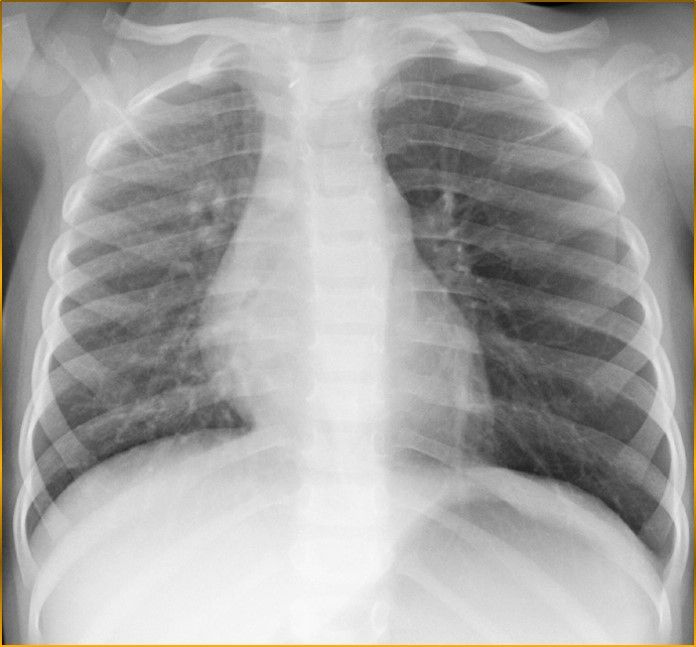

In questi casi la radiografia dl torace, eseguita in inspirio ed espirio, aiuta nell'individuazione della regione colpita .

Radiografia del Torace in inspirio

Si intravede alterazione della diafania del campo polmonare sinistro

Radiografia del Torace in Espirio

Si vede chiaramente la mancata espulsione dell'aria dal campo polmonare a sinistra per occlusione bronchiale